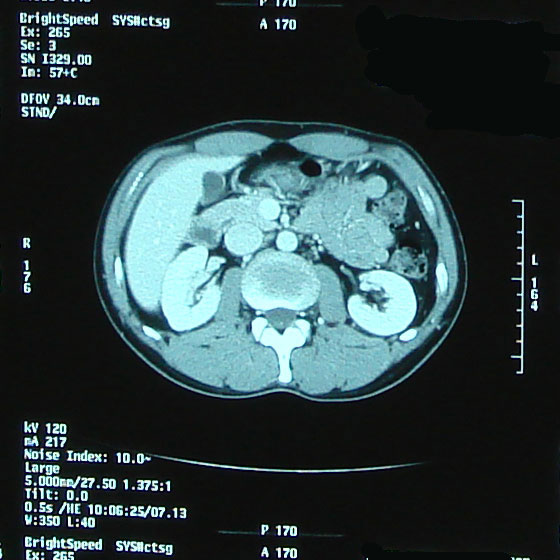

でも、髪質は脱毛前とは全く異なり、硬く、クセの強い、ゴワゴワしたものだった。 いろいろな人の体験記を読んでいたので、そうなるかもしれないこともわかっていたし、実際に抗癌剤治療をしたのだから「ま、そうだろうな」と思っていた。 でも、ここ最近ちょっと様子が変わったらしい。 今日、再び美容室に行った。 美容師さん:「少し柔らかくなったような・・以前はもっとこう・・何と言うか・・」 自分:「硬くてゴワゴワしてましたよね。」 少し髪質が柔らかくなってきたみたい。 いや、治療前の髪質に戻り始めたかな。 髪で風を感じるようになってきたのがちょっぴりうれしい最近です。 先日撮影したCT、採血結果を聞いてきました。 【画像】:変化なし 【HCGΒ】:0.1> 普通に仕事をして、普通に疲れてますが、検査的には問題なし。 この病気、わりと仕事現役世代が多いと思うのですが、みなさん治療後はバリバリ働いているのだろうか。 それで大丈夫なのだろうか。 それにしてもCT画像を見るのはおもしろい。 生きたまま自分の内部が見れるんだから。 毎回診察時に「写真撮っていいですか?」が恒例になってきてる。 先生も「あぁ、どうぞ(苦笑)。あ、撮るならこっちかな。」とか言って該当するほうのフィルムを移動してくれる(笑)。 そうだ、この日は入院時にお世話になった看護士の○澤さんが外来で助手をしてた。 ほとんど話ができなかったけど、この場をかりて 「大変お世話になりました。本当に感謝してます。」